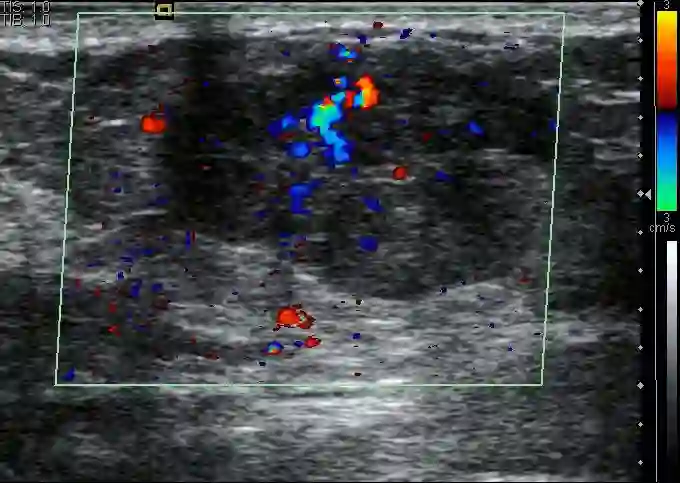

使用AI技术来检测乳腺癌,如今已有诸多研究,但大多是基于磁共振、乳腺X线影像进行预测。而 超声是中国女性乳腺癌筛查的主要方式 。如何利用好超声影像,进行乳腺癌筛查,并对乳腺癌做分子亚型分类,是中国AI医疗领域一个重要且有待拓展的方向。

亚洲女性的乳腺密度相对致密,对于致密型乳腺,超声相较于乳腺X线有较高的敏感性,且对人体没有辐射伤害。 因此在中国,大多体检会偏向于使用 超声。中国也是目前世界范围内乳腺癌超声数据最为丰富的国家。”

当然通过这种方式,医生仅能得出一个良/恶的初步判断, 对于乳腺癌的分子亚型,人眼是无法察觉的。

乳腺癌超声图像预测

而作为对比,SonoBreast,只需要将一张超声图片输入,便可以在几秒钟之内获得分子亚型的分类结果。目前,研究团队已经发布了Web端接口( open.baai.ac.cn/sonobreast ),任何人都可以上传超声图像,从而获得一个可借鉴的预测结果,这个结果包含了对每种亚型的预测置信度。